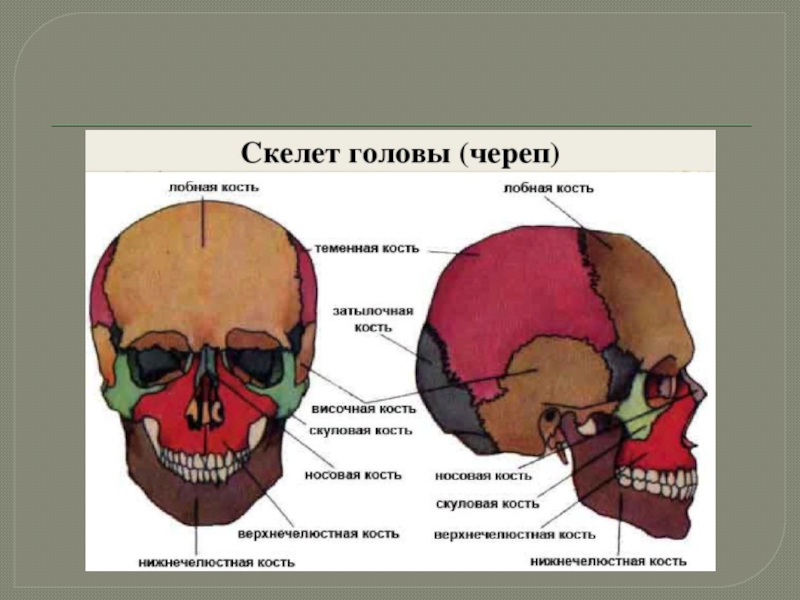

Анатомические изображения срединной сагиттальной линии черепа